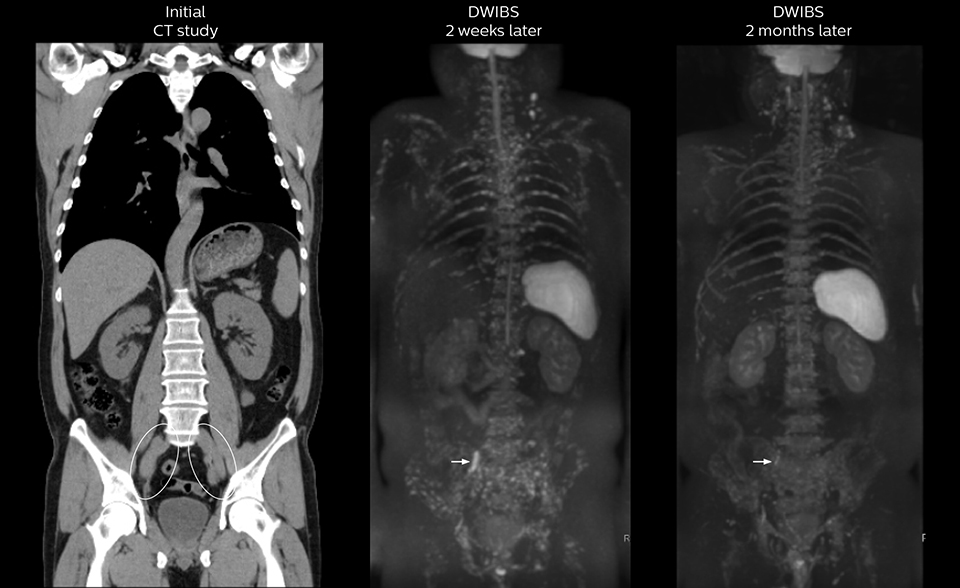

Recognizing the clinical utility of whole body MR imaging, radiologists at Kawasaki Saiwai Hospital (Kasawaki, Japan) began offering whole body diffusion weighted imaging (DWI) in 2009 for oncology patients. In 2012, the hospital installed a Philips scanner, the Ingenia 1.5T. The dStream digital architecture and highly linear gradients of Ingenia allowed them to switch to coronal – rather than axial – whole body DWI, and were key to developing a fast, high quality protocol that has led to increased referrals and decreased dependence on nuclear medicine imaging.

Radiologist Hiroshi Nobusawa, MD, PhD, explains that the coronal DWIBS protocol for whole body DWI is excellent for visualizing lesions in oncology patients. “About 90% of the DWIBS exams are done in this type of patients. The remainder of DWIBS exams are performed to gain information in cases of fevers of unknown origin,” he says.

“The DWIBS sequence’s value in oncology cases is due to the high contrast it creates between lesions and surrounding tissue. Whole body DWI is requested by physicians who need to clarify TNM staging or determine therapeutic strategies, oncologists in need of diagnosis or follow-up scans, surgeons who need to see the presence of distant lesions that are sometimes difficult to detect by CT before surgery, and urologists for the evaluation of bone lesions, and the effect of chemotherapy and radiotherapy.”

Shorter exam time needed for improving patient acceptance

“Before we had Ingenia, clinical adoption was hindered because the exam length of the whole body DWI protocol on our old system was difficult for many patients to tolerate,” says Takanori Naka, MR technologist.

“In our initial whole body DWI, we scanned from the top of the head to the toe in axial orientation. Because that took a lot of time, it constrained the examination to performing only coronal TSE and the axial whole body DWI scans. So, we had to compromise on clinical information to keep the exam to a reasonable length.”

Coronal DWIBS is faster and improves image quality

“Switching to coronal DWIBS – rather than axial – further shortens scan time,” says Mr. Naka. “Important is that a dS SENSE factor of 5 shortens exam time while high image quality can be maintained, thanks to Ingenia’s dStream architecture.” He adds that the coronal orientation also avoids artifacts that are specific to combining axial images.

“When we use a coronal DWIBS acquisition, we can perform a full whole body examination, including other required sequences, within 30 minutes,” he says.

“This is considerably faster than the previously used exam with axial whole body DWI, which took more than 45 minutes,” he notes. “A shorter exam is more patient-friendly and allows us to also use it on patients in poor health who would have difficulty tolerating a long exam. Limiting the exam time is also helpful for scheduling, because it fits in a normal single exam timeslot.”